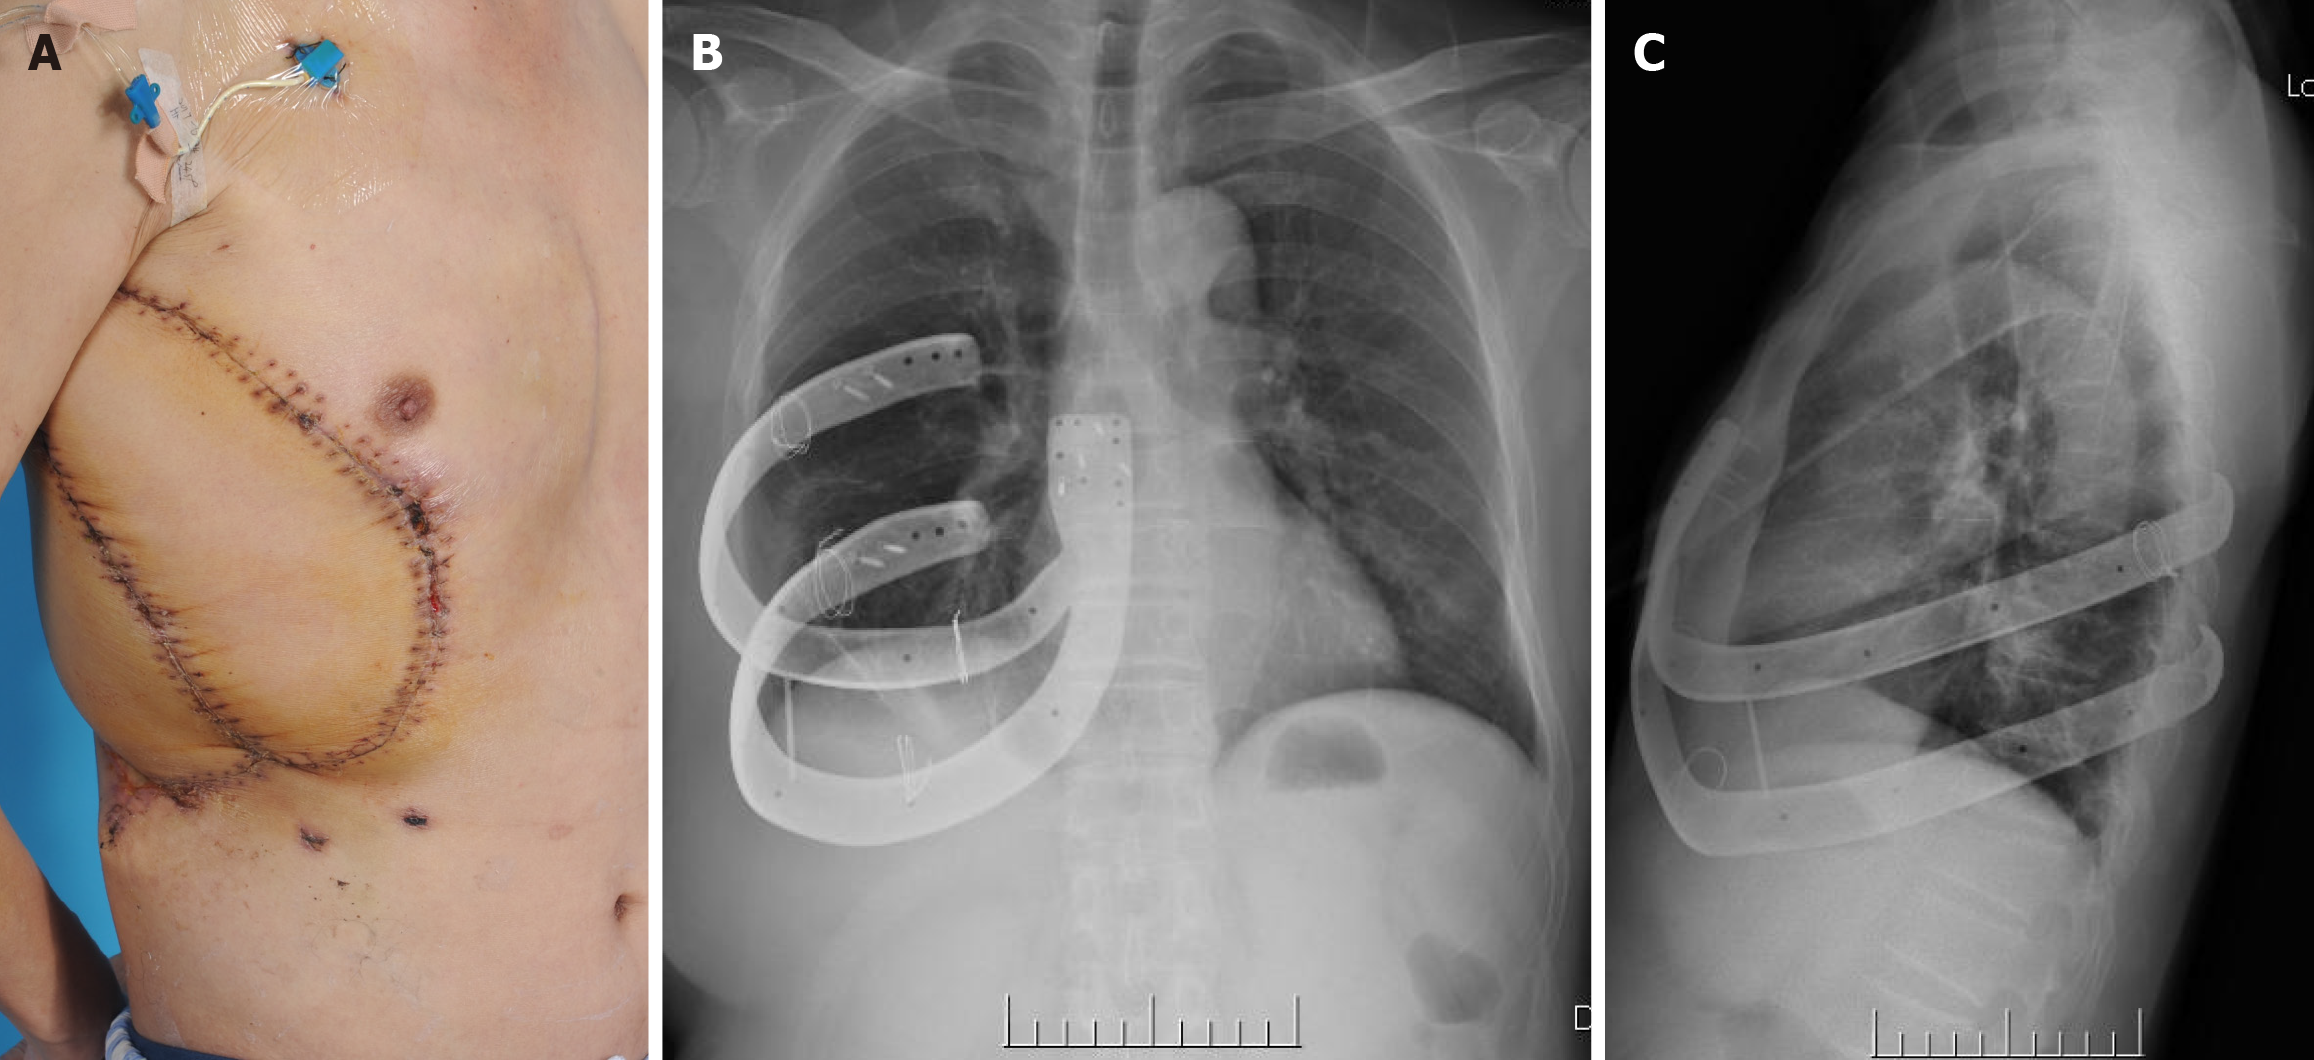

To overcome the challenge of having a massive defect of the chest-abdomen wall and exposure of internal organs after tumor resection, including thoracic defects and massive skin and soft tissue elimination, orthopedic, head, and neck microsurgery, and thoracic surgeons developed a combined solution. This was accomplished by reconstructing the stable and integral thoracic cavity with a 3D metal printing thoracic consisting of two ribs and a superior segment of sternum (Figure 2), as well as reconstructing the skin and soft tissue with two anterolateral thigh musculocutaneous flaps from the bilateral thigh.

To maintain a relatively aseptic environment, the ulcer wound dressings were changed every day before surgery. The patient’s albumin level and anti-infection capacity were supported by discontinuous transfusion of packed red blood cells and plasma. Prior to surgery, hemoglobin should be above 90 g/L, and albumin should be above 30 g/L. During general anesthesia, the patient was placed in the left lateral position. An extended round-shaped incision was carried out 3 cm away from the tumor edge via a combined thoracic and abdominal approach (Figure 3A). Lesions distributed in the skin, chest wall muscle, inferior angle of the scapula, parts of the 5th-12th ribs, and part of the diaphragm and liver capsular were all completely removed (Figure 3B). Fortunately, though the capsular could not be distinguished from the images (Figure 3B), it appeared intact and without obvious invasion. The resected lesion was 33 cm × 28 cm × 15 cm in size (Figure 3C). The small lung lesion was also resected during the routine thoracic exploration. Axillary lymph nodes were cleaned up by lengthening the incision up to the axillary fossa. Then, the deficient pleura and the liver capsular were repaired by sewing a nylon mesh along the edge of the left capsular. The 3D printed metal rib prosthesis was implanted and fixed with matched screws and metal wire to the other end of the left normal thoracic (Figure 3D). The defect area was approximately 22 cm × 34 cm.

The patient received antibiotics, fluid, and blood transfusions after the operation until a healthy internal environment and healthy flaps were confirmed. No postoperative complications such as bleeding, pneumothorax, abdominal infection, or vessel crisis or flap necrosis were displayed. The patient was in good condition and discharged 14 days after surgery, when the wound was confirmed to be well healed (Figure 5).

During 3 years of follow-up, no prosthesis displacement, infection, or respiratory complications were observed, in